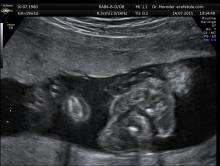

Fetal urination

The fetus urinates hourly and produces most of the amniotic fluid in the second and third trimester of pregnancy. The amniotic fluid is then recycled by fetal swallowing.[29]